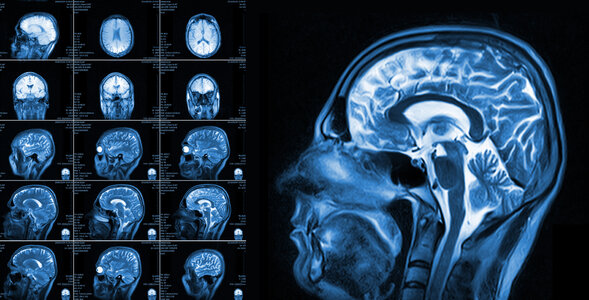

Guz mózgu

Guz mózgu to nic innego jak nowotwór tego organu. Objawy tego stanu chorobowego mogą różnić się w zależności między innymi od umiejscowienia. Jak wygląda leczenie i czy można mu zapobiegać?